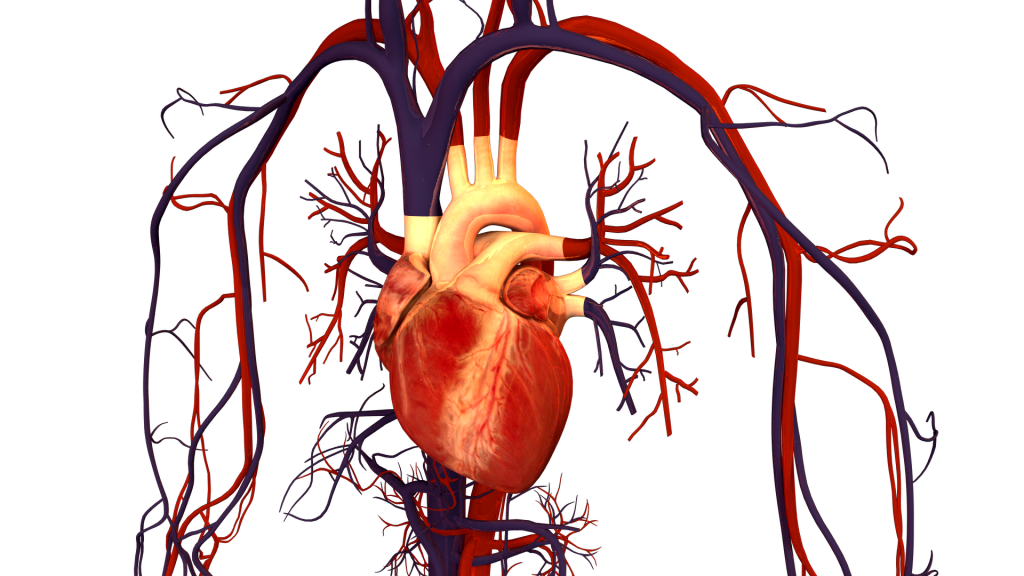

Krvný obeh

Jeden z najdôležitejších objavov v medicíne, objav krvného obehu, sa pripisuje anglickému lekárovi Williamovi Harveymu, ktorý v roku 1628 ako prvý úplne opísal systémový obeh a vlastnosti krvi, ktorú srdce pumpuje do mozgu a tela.